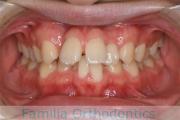

No.19V-044

- 上顎前突

- 13歳

- 女性

- 上:

- 44

- 下:

- 8558

- 主な使用装置:

- FEA

- 治療にかかった費用:

- 85万円

出っ歯を治したいということで小学生の時に来院されました。中学生になるまで経過観察をして、診断、上下左右から小臼歯を抜歯してマルチブラケット法にて治療を行いました。2年強、30回程度の通院が必要でした。

口元の突出感も大きく改善しています。

右側

正面

左側

上下とも前歯の叢生(でこぼこ、凹凸、ガタガタ)がありましたので、保定をしっかりやらないと後戻りのリスクが出てきます。